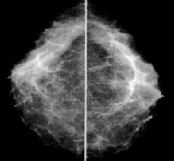

Com uma vasta linha de equipamentos Bennett instalados no Brasil, atendemos desde os robustos aparelhos de Raio X de alta freqüência da linha HFQ e VIP até os excelentes mamógrafos Contour Plus, Contour 2000, e MF150 (Foto). Este ultimo foi o modelo Bennett de maior penetração no mercado nacional.

Bennett MF150